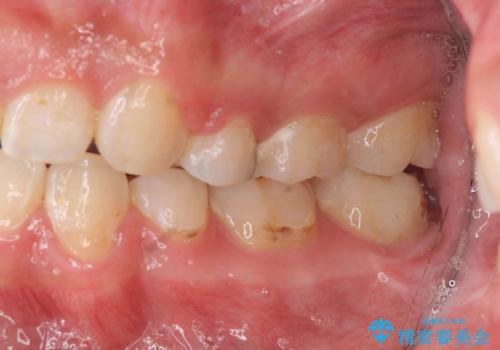

上の歯並びが前にずれて、さらに前歯が内側に倒れて過蓋咬合を呈していました。

奥歯のかみ合わせもずれていたため、上の奥歯を後ろに下げる処置をミニスクリューを用いて行いました。